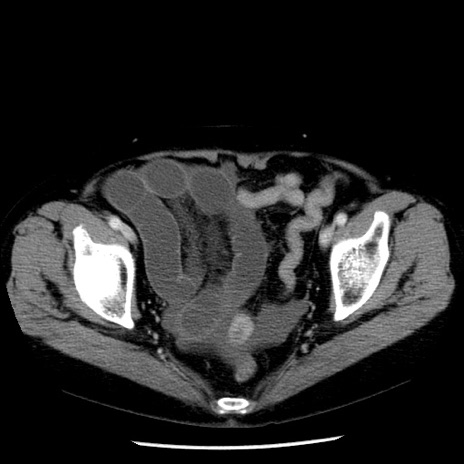

症例13(横断像)

【症例】70歳代女性

【主訴】腹痛、嘔吐

【現病歴】15時間程前(昨晩)より腹痛あり。今朝になっても症状の改善なく、嘔吐あり。腹痛も増悪あり、救急外来受診。

【既往歴】子宮癌全摘術後

【身体所見】意識清明、BP 121/72mmHg、P 74bpm、SpO2 100%(RA)、腹部:平坦・軟、腸雑音ほぼ聴取せず。下腹部・心窩部・臍左上に圧痛あり。反跳痛なし。

【データ】WBC 10600、CRP 0.15